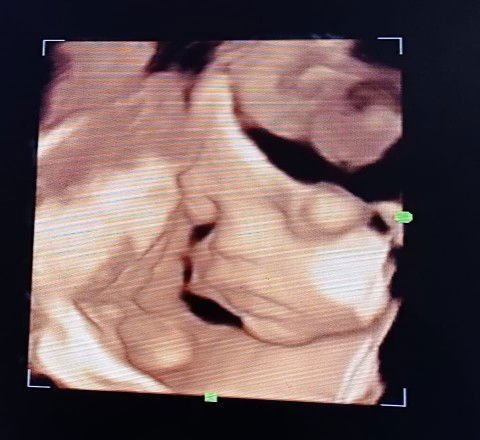

Usia 28 weeks ada kah yang sama dg sy sering kenceng?? USG 4D kemarin Alhamdulillah bayi sehat🤲🤲

USG 4D kemarin Alhamdulillah bayi sehat🤲🤲